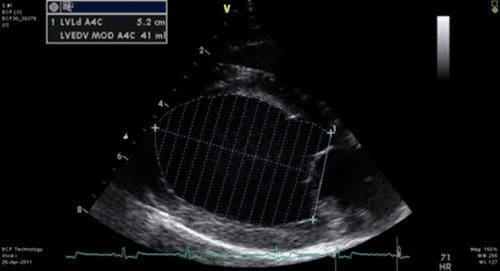

Right parasternal long axis view (4 chamber view)

Measurement on frozen B-mode image

Simpson’s rule used to evaluate left ventricular volume

2 measurements made during diastole and 2 measurements taken during systole

Diastole

– LVLd (Left ventricle length during diastole)

– LVAd (Left ventricle area during diastole)

Systole

– LVLs (Left ventricle length during systole)

– LVAs (Left ventricle area during systole)

Machine will calculate Ejection fraction (will also display EDV and ESV – End diastolic

volume and End systolic volume)

Normal value – >50% in normal dog

Decreased in DCM (heart contracting poorly during systole)